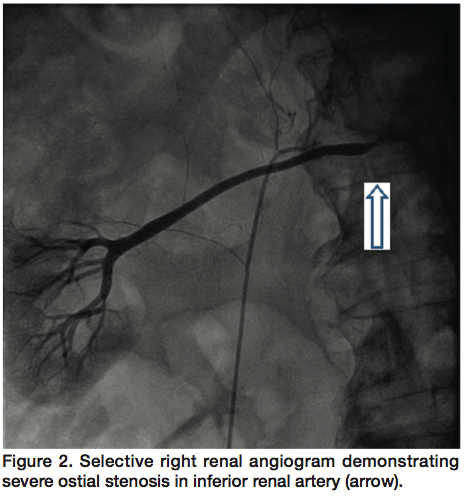

Based on these results, simultaneous percutaneous intervention of both right renal arteries was performed. After obtaining access in both common femoral arteries, two 7 Fr Renal Double Curve guide catheters (Cordis Corporation) were simultaneously engaged into the 2 renal arteries. We gave the patient 7000 units of heparin intravenously, which resulted in an activated clotting time of 276 seconds. We placed 0.014-inch diameter Asahi prowater guidewires (Abbott Vascular) distally and crossed the stenosis in each renal artery. Using two 2.5 mm x 8 mm Quantum Apex non-compliant balloons (Boston Scientific), simultaneous kissing balloon angioplasty of both renal arteries was performed at 12 atm (Figure 3). However, the lesion in the superior renal artery failed to yield, requiring another angioplasty at 20 atm using the same balloon. Subsequently, serial stenting of the 2 renal arteries was performed using 2 Liberté Rx bare metal stents (Boston Scientific): 3.5 mm x 12 mm for the superior and 3 mm x 12 mm for the inferior renal artery. Final angiography revealed well-expanded stents in both renal arteries with <20% residual stenosis in the inferior (Figure 4). There was no residual stenosis in the superior renal artery (Figure 5). There was no distal embolization, and no dissection.